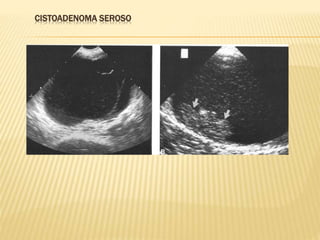

CISTOADENOMA SEROSO

TUMORES EPITELIALES  Cistoadenomaseroso (carcinoma)  Cistoadenoma mucinoso (carcinoma)  Carcinoma endometroide  Carcinoma de células claras  Tumor de células transicionales  INCIDENCIA : 65 % AL 75%